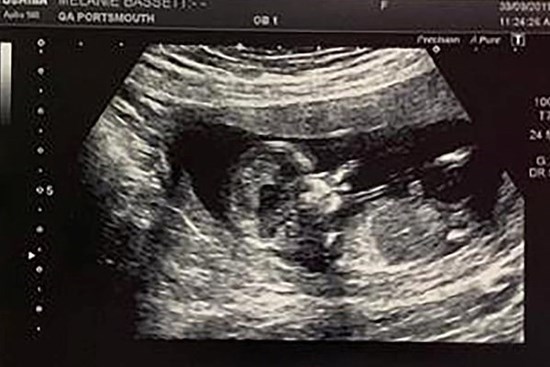

Siêu âm ở tuần thứ 8 phát hiện có 2 tim thai, nhưng đến tuần thứ 12, cặp vợ chồng sửng sốt khi nghe bác sĩ nói câu này

Trên thế giới hiện nay mới chỉ có 4 trường hợp này và bác sĩ tin rằng chị Melanie là trường hợp đầu tiên ở nước Anh.

Kỳ lạ mẹ bầu mang song thai, nhưng là trong 2 tử cung khác nhau

Đây đúng là trường hợp mang thai có một không hai khi theo các bác sĩ, cứ 50 triệu người thì may ra mới phát hiện 1 trường hợp.